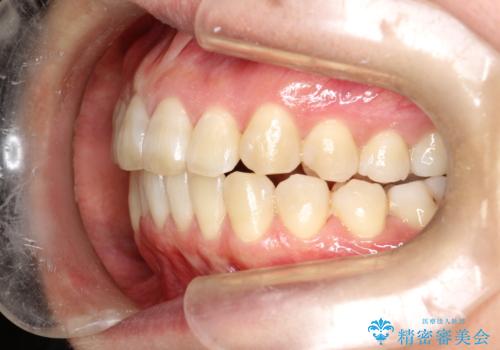

インビザラインによる矯正治療(非抜歯) 前歯の突出と上下の歯並びのガタつきの改善

- 上下の歯並びにガタつきがあり、また、上下前歯の前後のズレが大きく上の前歯が突出しています。

インビザラインではガタつき(叢生)の改善だけでなく、上下の前後的なズレについてもアプローチが可能です。

インビザラインの特色を生かした歯牙移動計画を作成し、非抜歯にて治療を行いました。

概ね2年での治療完了となりました。

当院独自の工夫を随所に盛り込み、狙い通りの治療結果が得られました。